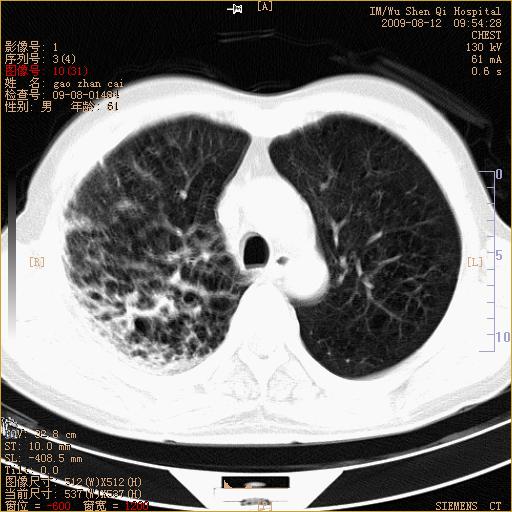

1、右上肺继发性肺结核合并感染;2、肺气肿。

右肺间质纤维化右肺间质性肺炎

右肺上叶干酪性肺炎

右肺弥漫性间质性改变

考虑右肺间质性肺炎并右侧胸膜炎可能性大。

右上肺干酪性肺炎,肺气肿

考虑右肺支扩并感染可能,结核不除外,结核生化检查看看。

右肺间质性肺炎,肺气肿

考虑右肺结核, 右肺间质性改变,肺气肿。

右肺上叶支扩并感染,肺间质纤维化。

1)右肺上叶感染性病变;建议抗炎治疗后复查。2)肺气肿。

右肺上叶支扩并感染,肺间质纤维化,肺气肿,右肺门淋巴结肿大。建议抗炎治疗后复查。